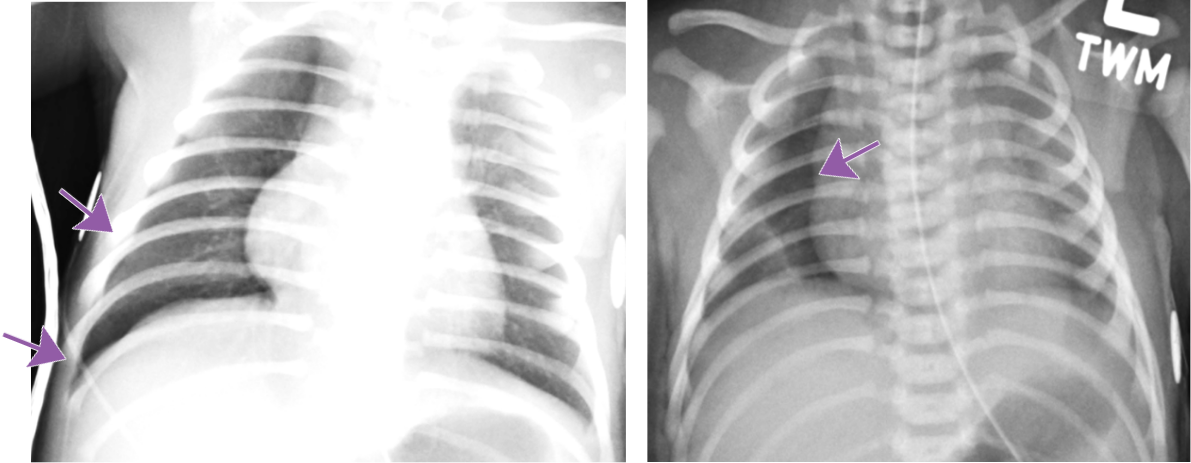

Anterior Pneumothorax

Hallmarks: Deep sulcus sign, no lung marking at the edge of right lung, increased sharpness of the cardiomediastinal border, more prominent on expiration.

May be bilateral.

Can occur in both term and preterm babies.

Compare lung lucency between both sides.

Decubitus radiograph can be a helpful tool for confirmation.